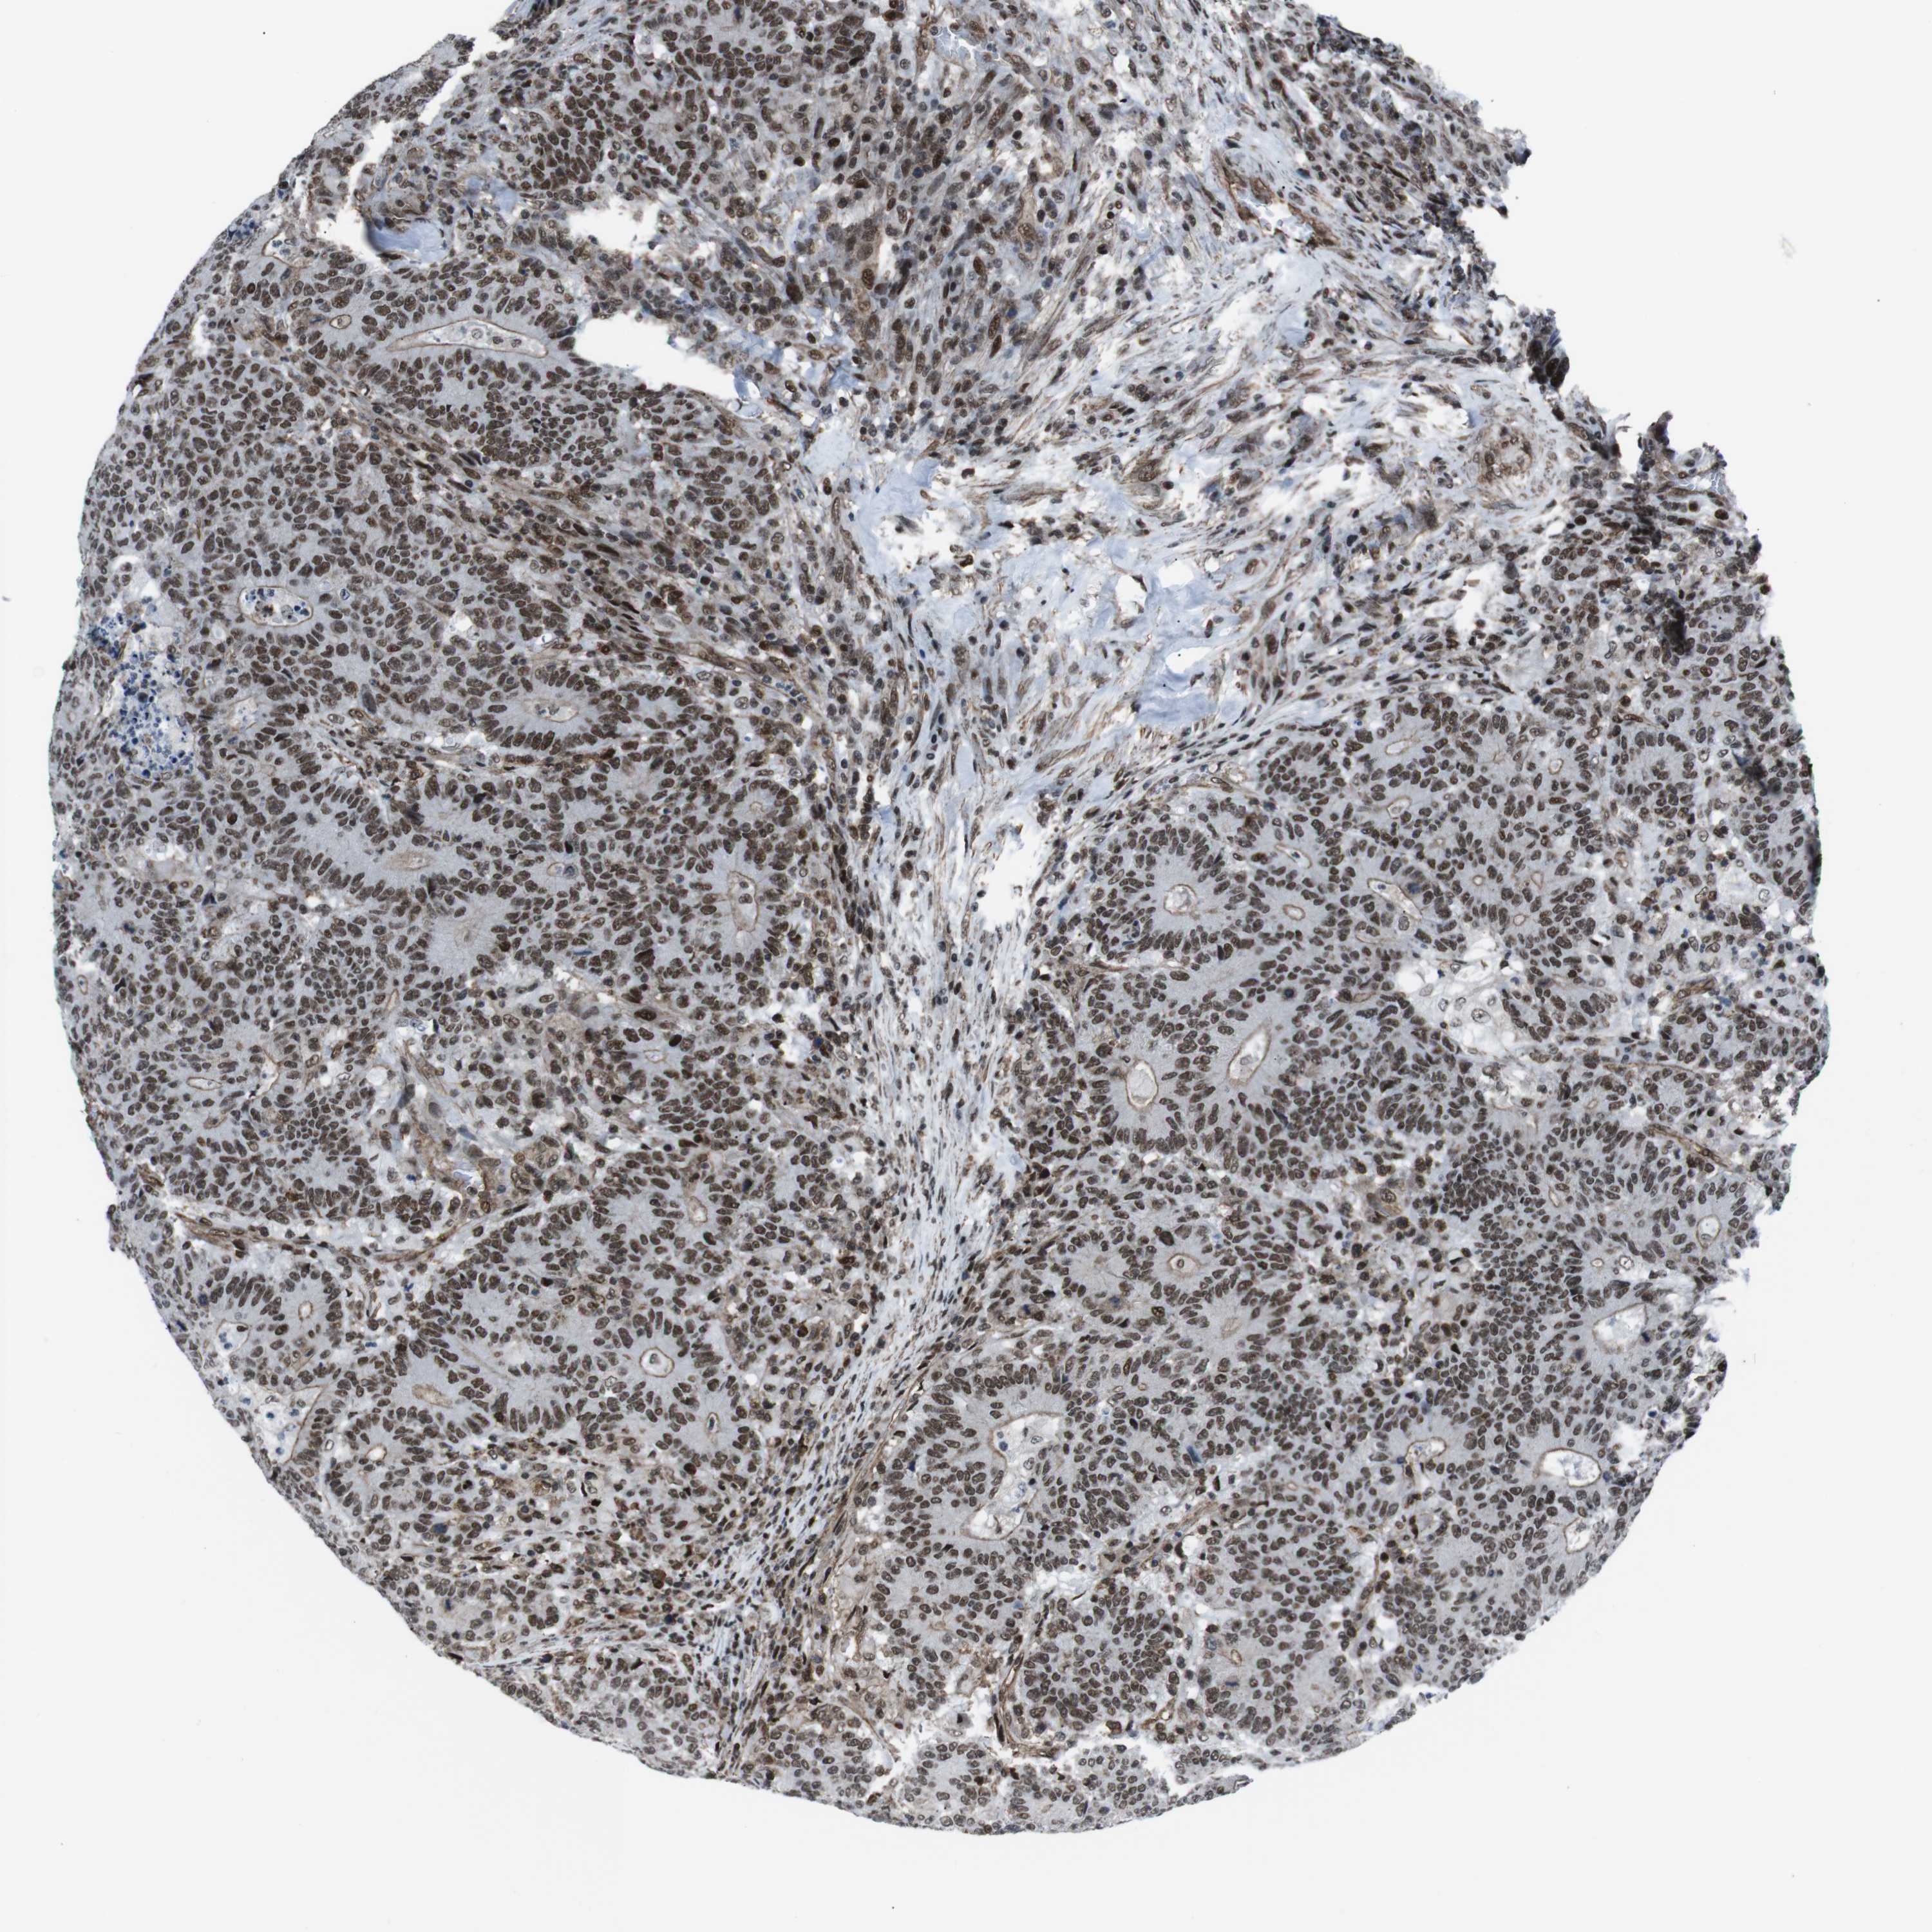

CANCER COLORECTAL CANCER Show tissue menu

Colorectal cancer

Human cancer

Colon adenocarcinoma